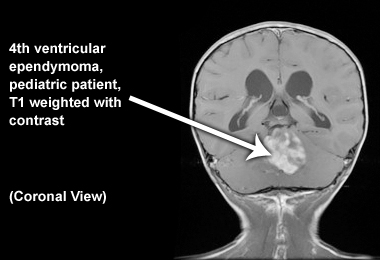

Coronal image

Below is an image of fourth ventricular ependymoma in a pediatric patient (T1 weighted with contrast):